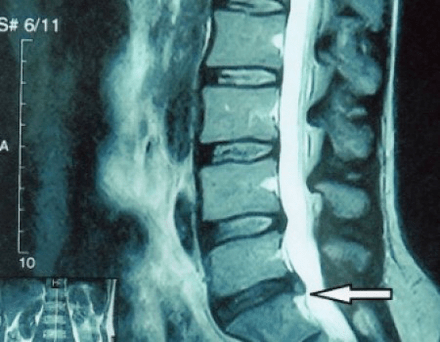

osteocondroza regiunii vertebrale la radiografie

În cazuri tipice, osteocondroza coloanei vertebrale cervicale și cervico-toracice apare așa cum este descris mai sus. Prin urmare, etapa principală a diagnosticului a fost și rămâne identificarea plângerilor pacientului, stabilirea prezenței spasmului muscular concomitent prin simpla palpare a mușchilor de-a lungul coloanei vertebrale. Este posibil să se confirme diagnosticul de osteocondroză folosind examenul cu raze X?

O „radiografie” a coloanei cervicale și chiar și cu teste funcționale pentru flexie și extensie, nu arată cartilaj, deoarece țesutul lor transmite raze X. În ciuda acestui fapt, pe baza locației vertebrelor, se pot trage concluzii generale despre înălțimea discurilor intervertebrale, îndreptarea generală a curburii fiziologice a gâtului - lordoză, precum și prezența excrescentelor marginale pe vertebre cu iritarea prelungită a suprafețelor acestora de către discurile intervertebrale fragile și deshidratate. Testele funcționale pot confirma diagnosticul de instabilitate la nivelul coloanei cervicale.

Deoarece discurile în sine pot fi văzute numai folosind CT sau RMN, rezonanța magnetică și tomografia computerizată cu raze X sunt indicate pentru a clarifica structura internă a cartilajului și a formațiunilor cum ar fi proeminențele și herniile. Astfel, cu ajutorul acestor metode se face un diagnostic cu acuratețe, iar rezultatul tomografiei este o indicație, și chiar un ghid de actualitate, pentru tratamentul chirurgical al unei hernii în secția de neurochirurgie.